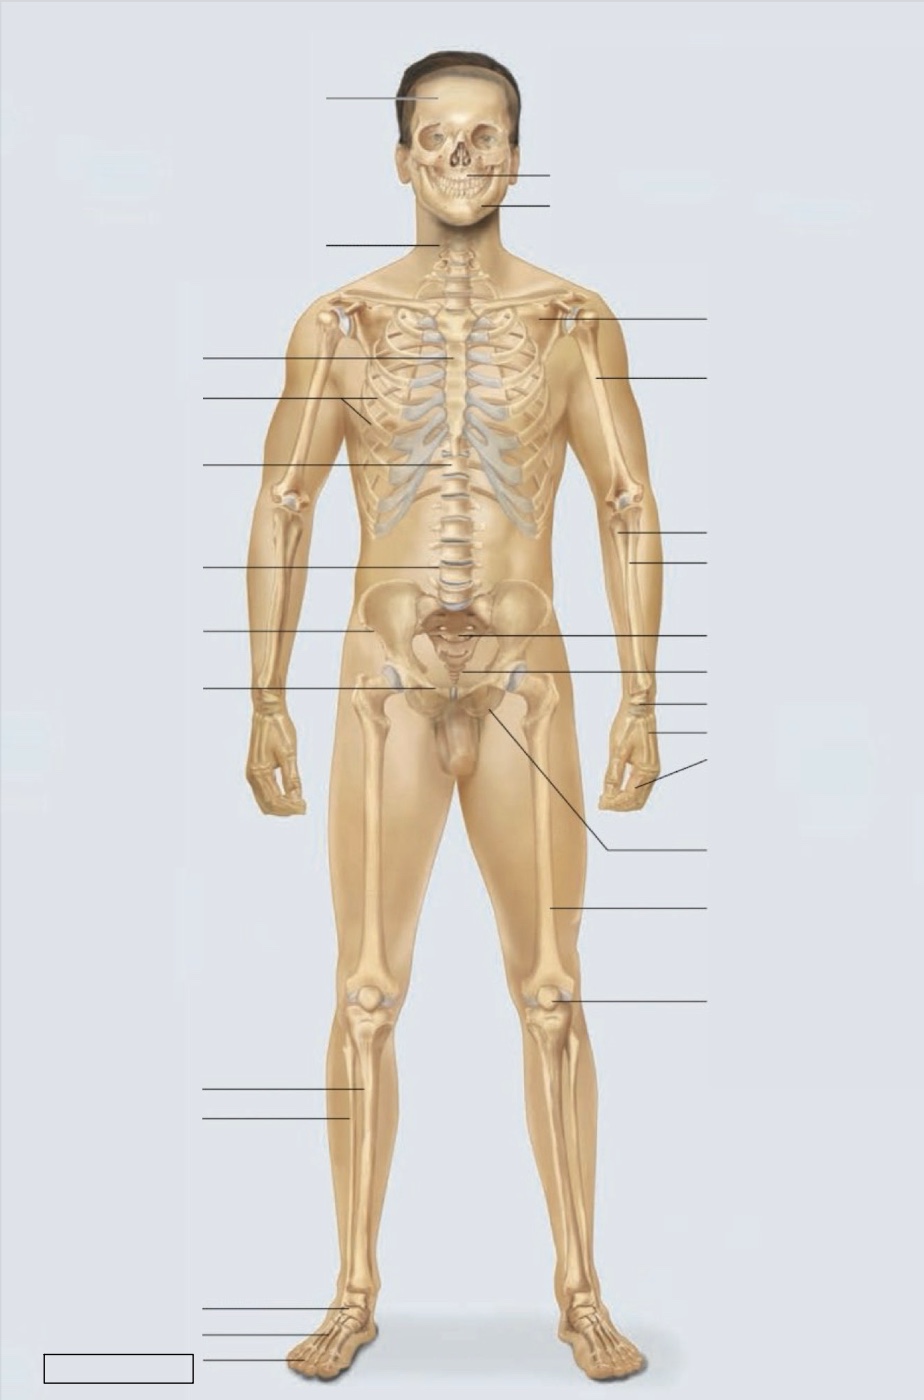

maxilla

mandible

scapula

humerus

ulna

radius

sacrum

coccyx

carpals

metacarpals

phalanges

ischium

femur

patella

phalanges

metatarsals

tarsals

fibula

tibia

pubis

ilium

lumbar vertebrae (L4)

thoracic vertebrae (T11)

ribs

sternum

cervical vertebrae

skull